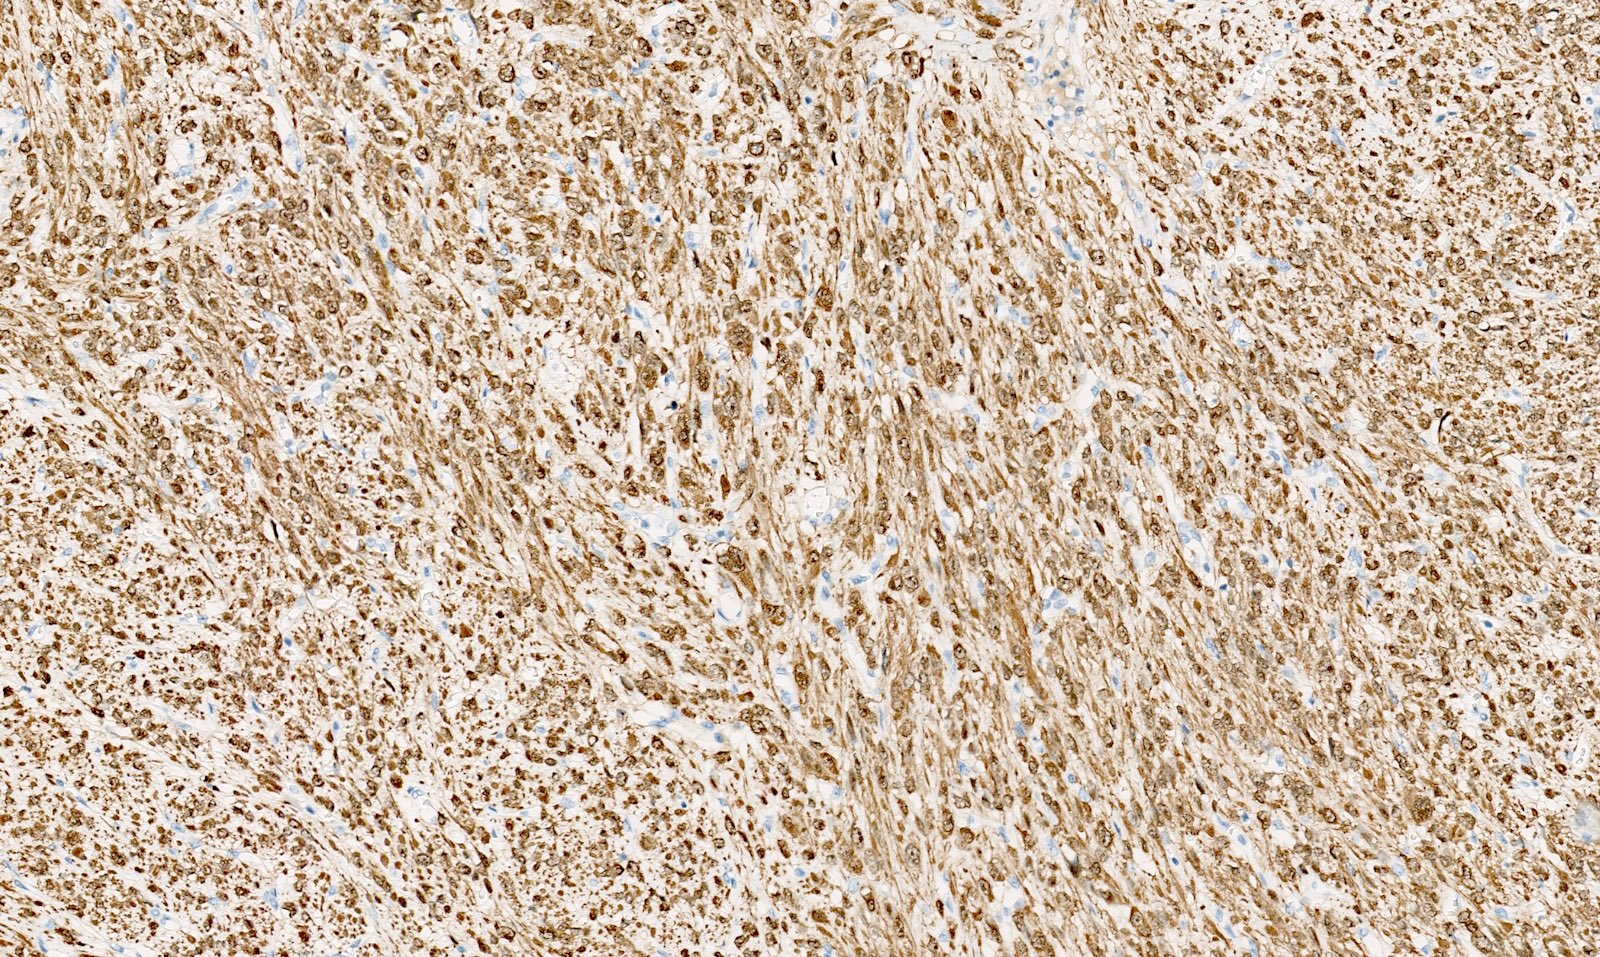

Microscopic (histologic) images

Contributed by Sabrina Croce, M.D., Ph.D., Kristina Doytcheva, M.D., Jennifer A. Bennett, M.D. (Case #508) and @Andrew_Fltv on Twitter

Positive stains

- Desmin

- h-caldesmon

- Smooth muscle actin

- Transgelin

- Smooth muscle markers can be weak in epithelioid and myxoid leiomyomas

- Estrogen and progesterone receptors

- WT1

- Up to 40% of leiomyomas are CD10 positive (especially cellular leiomyomas) (Am J Surg Pathol 2002;26:403)

- FH loss of expression and 2SC positivity may be useful to identify fumarate hydratase deficient leiomyoma (Am J Surg Pathol 2016;40:599, Mod Pathol 2014;27:1020)

- FH loss of expression is specific of FH deficient leiomyoma but its sensitivity is low with different results across different leiomyomas of the same patient; for these reasons, the clinical value of FH staining is limited (Am J Surg Pathol 2015;39:1529, Am J Surg Pathol 2019;43:1170, Genes Chromosomes Cancer 2021;60:210)

- 2SC nuclear staining has been reported in FH deficient leiomyomas but is not widely commercially available and experience is limited (Am J Surg Pathol 2014;38:627, Am J Surg Pathol 2015;39:1529, Mod Pathol 2014;27:1020, Genes Chromosomes Cancer 2020 Oct 24 [Epub ahead of print])